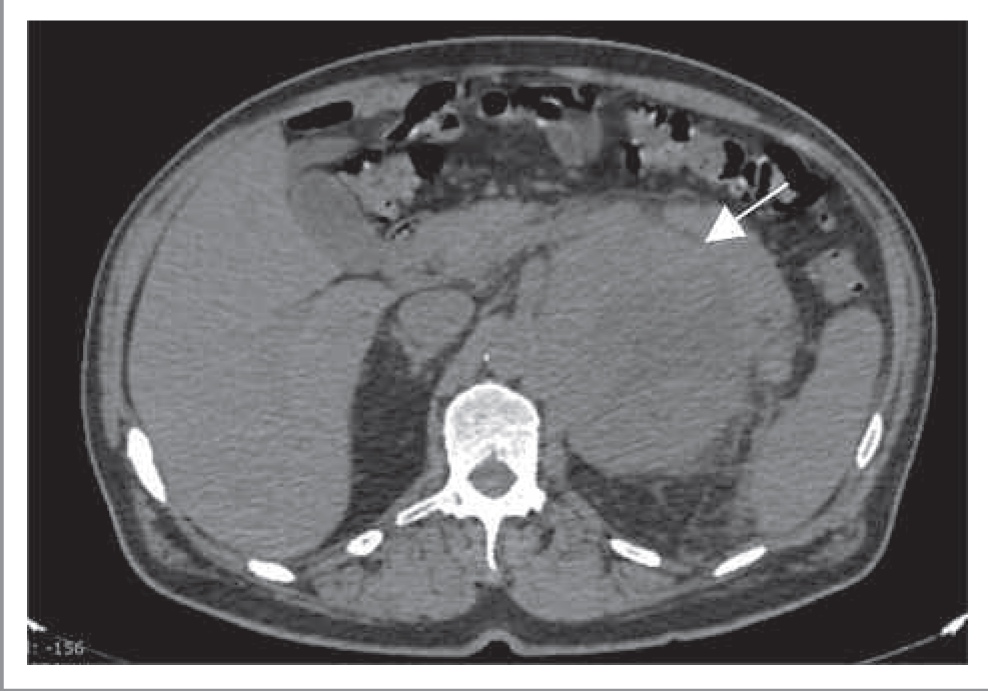

Кровоизлияние в надпочечник (гематома). Причин кровоизлияния в надпочечник множество, однако основной является физиологический стресс, например шок, сепсис, оперативное вмешательство, гипотензия, венозная гипертензия (тромбоз надпочечниковой или нижней полой вены), антикоагуляция и геморрагические диатезы. У новорожденных кровоизлияние диагностируют чаще по сравнению с детьми более старшего возраста и взрослыми [17]. Острое или подострое кровоизлияние характеризуется наличием высокой плотности (60–90 ед. Н) округлого или овального образования различного размера, не накапливающего контрастный препарат. При динамическом наблюдении размер данного образования уменьшается, а плотность снижается, что обусловлено лизированием гематомы. Через год данное образование может обызвествляться. Для хронической гематомы характерно наличие жидкостного образования с тонкой псевдокапсулой по периферии и кальцинатами в структуре. Двустороннее расположение гематом чаще определяется при системных патологических процессах (шок, сепсис), в то время как одностороннее кровоизлияние чаще является следствием тупой травмы. При этом чаще кровоизлияние обнаруживают в правом надпочечнике, что связано со сдавлением его между печенью и правой почкой.

При обнаружении кровоизлияния в надпочечнике следует тщательно изучить весь надпочечник, так как возможно обнаружение образования, в котором выявлено кровоизлияние (например, аденома, миелолипома, рак).